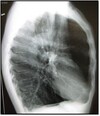

Q

What pathology is seen here?

A

Croup

How well did you know this?